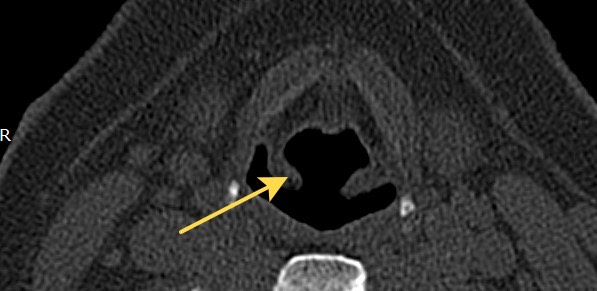

2415. Анатомическая структура, отмеченная на снимке, является